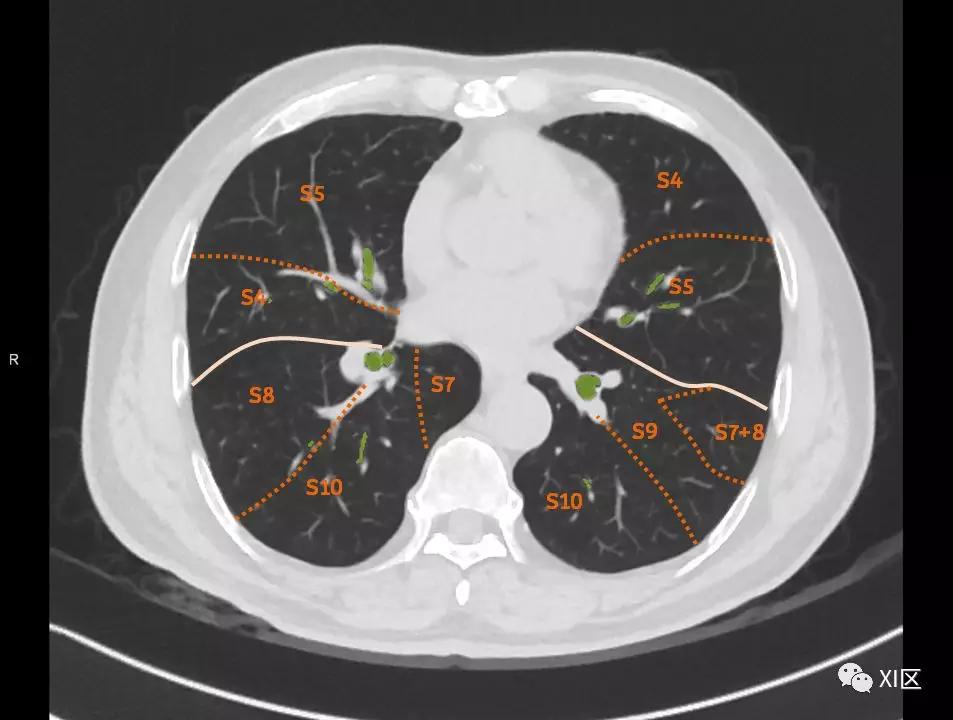

肺的断层分段示意图

在进行肺的分段时,可以上下观察浏览,沿着相应气管的走形可以更容易准确地进行分段。